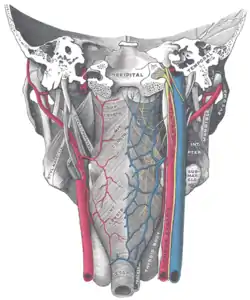

Muscles of the pharynx, viewed from behind, together with the associated vessels and nerves. (Inf. const. labeled at bottom center.) | |

Nerve supply

The inferior pharyngeal constrictor muscle can be supplied by branches from the pharyngeal plexus,[4] the recurrent laryngeal nerve, the external branch of the superior laryngeal nerve, or a combination of these (the recurrent laryngeal nerve being the most common innervation of the cricopharyngeal part).[5] All these branches and nerves come from the vagus nerve (CN X).[4]